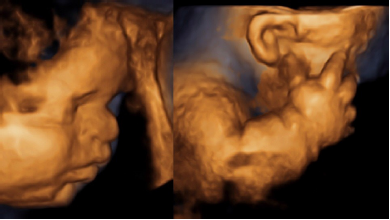

Se presenta el caso de una primigesta de 20 años de edad con 30 semanas de edad gestacional por ecografía precoz. Acudió al servicio de ecografía con diagnóstico de acondroplasia fetal, sin antecedentes personales ni familiares de importancia con relación a patologías de orden genético. Al examen ultrasonográfico se halló ponderado fetal de 2 323 g (p12 para la EG), fémur corto (p< 2DE) y curvo, tórax estrecho (circunferencia de 172 mm cortas, abdomen protuberante, macrocefalia DBP de 93 mm (>p 97,7%) CC de 319 mm (>p 97,7%), con cráneo en forma de trébol, frente prominente y aplanamiento nasal; relación fémur-pie de 0,4 (figuras 1 y 2). Otro hallazgo fue la presencia de polihidramnios leve (pozo mayor de 8,1 cm). No se encontraron malformaciones cardiacas. La reconstrucción 3D evidenció el acortamiento de los miembros superiores e inferiores y las características faciales (figura 3). De acuerdo a los hallazgos, se planteó el diagnóstico de TD, informando a la familia acerca del grave pronóstico del feto. El parto vaginal se dio una semana después, con un recién nacido vivo de sexo masculino de 2 015 g, Ápgar 2 al minuto y 5 a los 5 minutos, requiriendo intubación endotraqueal y soporte ventilatorio. Fue hospitalizado en UCI neonatal con el diagnóstico de insuficiencia respiratoria. El estudio radiográfico evidenció costillas acortadas, con los huesos largos de los miembros superiores e inferiores cortos y curvos (figura 4). El neonato falleció por insuficiencia respiratoria a los 7 días.

Se continúa con el estudio del cráneo fetal, evaluando la forma, tamaño de la cabeza y grado de mineralización; no se debe olvidar que muchas DE muestran macrocrania o deformaciones(6,7). Estas deformaciones del cráneo se producen por cierres prematuros de las suturas (craneo- sinostosis)(9); una de las más características es el cráneo en trébol, que en el caso se presentó pero como un fenotipo muy leve. La evaluación de la cara fetal debe ser completa, iniciando con el perfil fetal en busca de frente prominente, aplanamiento nasal o micrognatia; luego, se descarta lesiones de la línea media y defectos oculares (hipo o hipertelorismo)(10); característicamente, en la TD se observa frente prominente y aplanamiento nasal, como se observa en la figura 3. El siguiente paso sería la evaluación de la columna fetal, para descartar problemas de escoliosis, hemivértebras, deficiente mineralización o defectos del tubo neural(6,7,8).